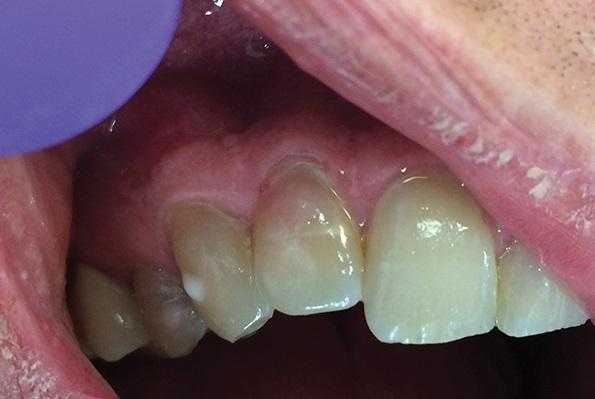

В исследование были включены 25 пациентов с диагнозом локальной рецессии, с клинической картиной, при которой отмечалась рецессия только у одного из идентичных зубов (рис. 1). Рис. 1. Исследование проводили у каждого пациента в области идентичных зубов. В данном случае: зуб 1.3 с рецессией, 2.3 — без рецессии. Исследовали 30 зубов, имеющих рецессию от 1,0 до 4,8 мм. Контрольная группа включала в себя 30 идентичных зубов с противоположной стороны, не имеющих рецессии (6 зубов имели минимальную потерю прикрепления — до 0,5 мм). Возраст пациентов составлял от 21 года до 36 лет, среди них было 13 женщин и 12 мужчин.

В большинстве случаев при определении таких клинических параметров, как высота КД и глубина рецессии, исследователи используют градуированный зонд или штангенциркули Кастровьехо с разрешающей способностью от 0,5 до 1 мм. Мы использовали стоматологическую гладилку, на которую нанесли лазерную насечку (рис. 2), Рис. 2. Масштабирование фотографий и расчет показателей высоты КД и величины рецессии. имеющую шаг 0,2 мм (200 мк), в целях повышения точности исследования. Глаз человека как естественный оптический прибор имеет определенную разрешающую способность [19], но работа с такими малыми величинами имеет значительную погрешность, поэтому для измерения мы использовали следующую методику: после окрашивания десны раствором Шиллера рядом с исследуемым участком прикладывали стоматологическую гладилку с лазерной насечкой. После фотографирования объекта в режиме макросъемки и масштабирования фотографий проводили расчет и фиксировали показатели измерения (рис. 2).

Клиническое исследование по описанной выше методике включало в себя определение величины рецессии и высоты КД.